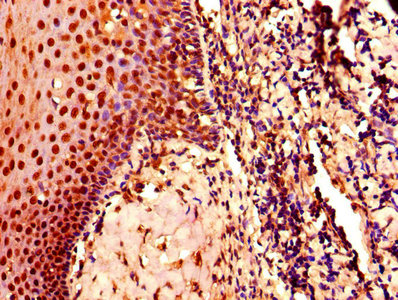

• IHC image of CSB-PA005061LA01HU diluted at 1:800 and staining in paraffin-embedded human tonsil tissue performed on a Leica BondTM system. After dewaxing and hydration, antigen retrieval was mediated by high pressure in a citrate buffer (pH 6.0). Section was blocked with 10% normal goat serum 30min at RT. Then primary antibody (1% BSA) was incubated at 4°C overnight. The primary is detected by a biotinylated secondary antibody and visualized using an HRP conjugated SP system.